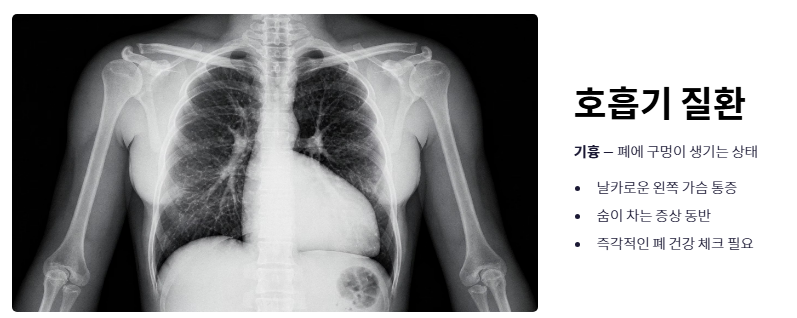

- 호흡기 및 심리적 요인 (기흉 및 공황장애): 폐에 구멍이 생기는 기흉이나 극도의 불안감이 동반되는 공황장애 역시 날카로운 왼쪽 가슴 통증 원인이 될 수 있습니다. 특히 숨이 차는 증상이 동반된다면 폐 건강을 체크해야 합니다.